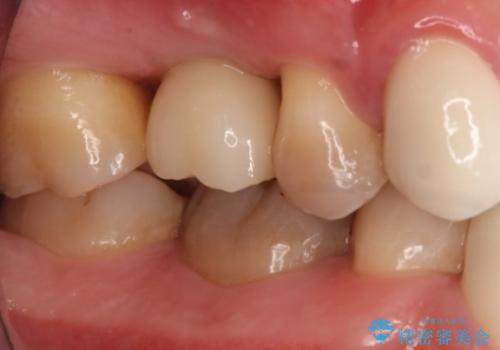

- 右上6番の歯の欠損部の治療を希望され来院された患者様です。

インプラント治療を希望されたので、インプラントとセラミッククラウンでの治療を計画しました。